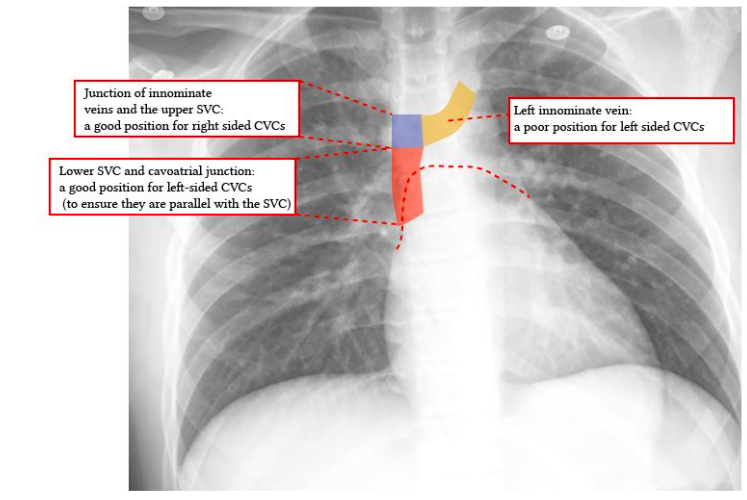

Screen Shot 2018-08-31 at 4.56.23 PM Published August 31, 2018 at 747 × 500 in VIVA AID: IDEAL POSITION OF TIP OF RIGHT IJV CATHETER ← Previous